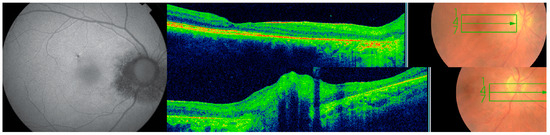

3.1. Case 1

3.2. Case 2

3.3. Case 3

3.4. Case 4